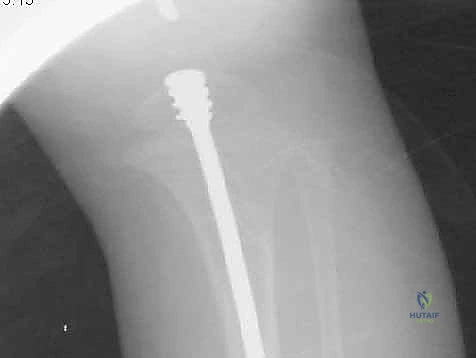

الدليل التفصيلي لخطوات العملية الجراحية: بضع العظم عبر الجلد والمسامير التلسكوبية

تُعد هذه العملية من أدق العمليات في جراحة عظام الأطفال، وتتطلب مهارة استثنائية كما هو الحال مع البروفيسور محمد هطيف. يتكون المسمار التلسكوبي (Fassier-Duval) من جزأين يتداخلان ببعضهما البعض (مثل التلسكوب). يتم تثبيت أحد الأطراف في أعلى العظم والطرف الآخر في أسفله. عندما ينمو العظم، ينزلق الجزء الداخلي من المسمار للخارج، مما يسمح للعظم بالنمو الطبيعي دون أن ينثني أو ينكسر.

الخطوة الرابعة: إدخال المسمار التلسكوبي

بعد تقويم العظم وجعله مستقيماً كحبات المسبحة على خيط، يتم إدخال السلك الدليلي (Guide Wire). ثم يتم إدخال الجزء الخارجي (الأنثوي) من المسمار التلسكوبي وتثبيته في الجزء العلوي من العظم (Epiphysis).

بعد ذلك، يتم إدخال الجزء الداخلي (الذكري) من المسمار عبر الجزء السفلي من العظم وتثبيته في المشاشة السفلية. هذا التصميم العبقري يضمن حماية العظم بالكامل من الداخل.